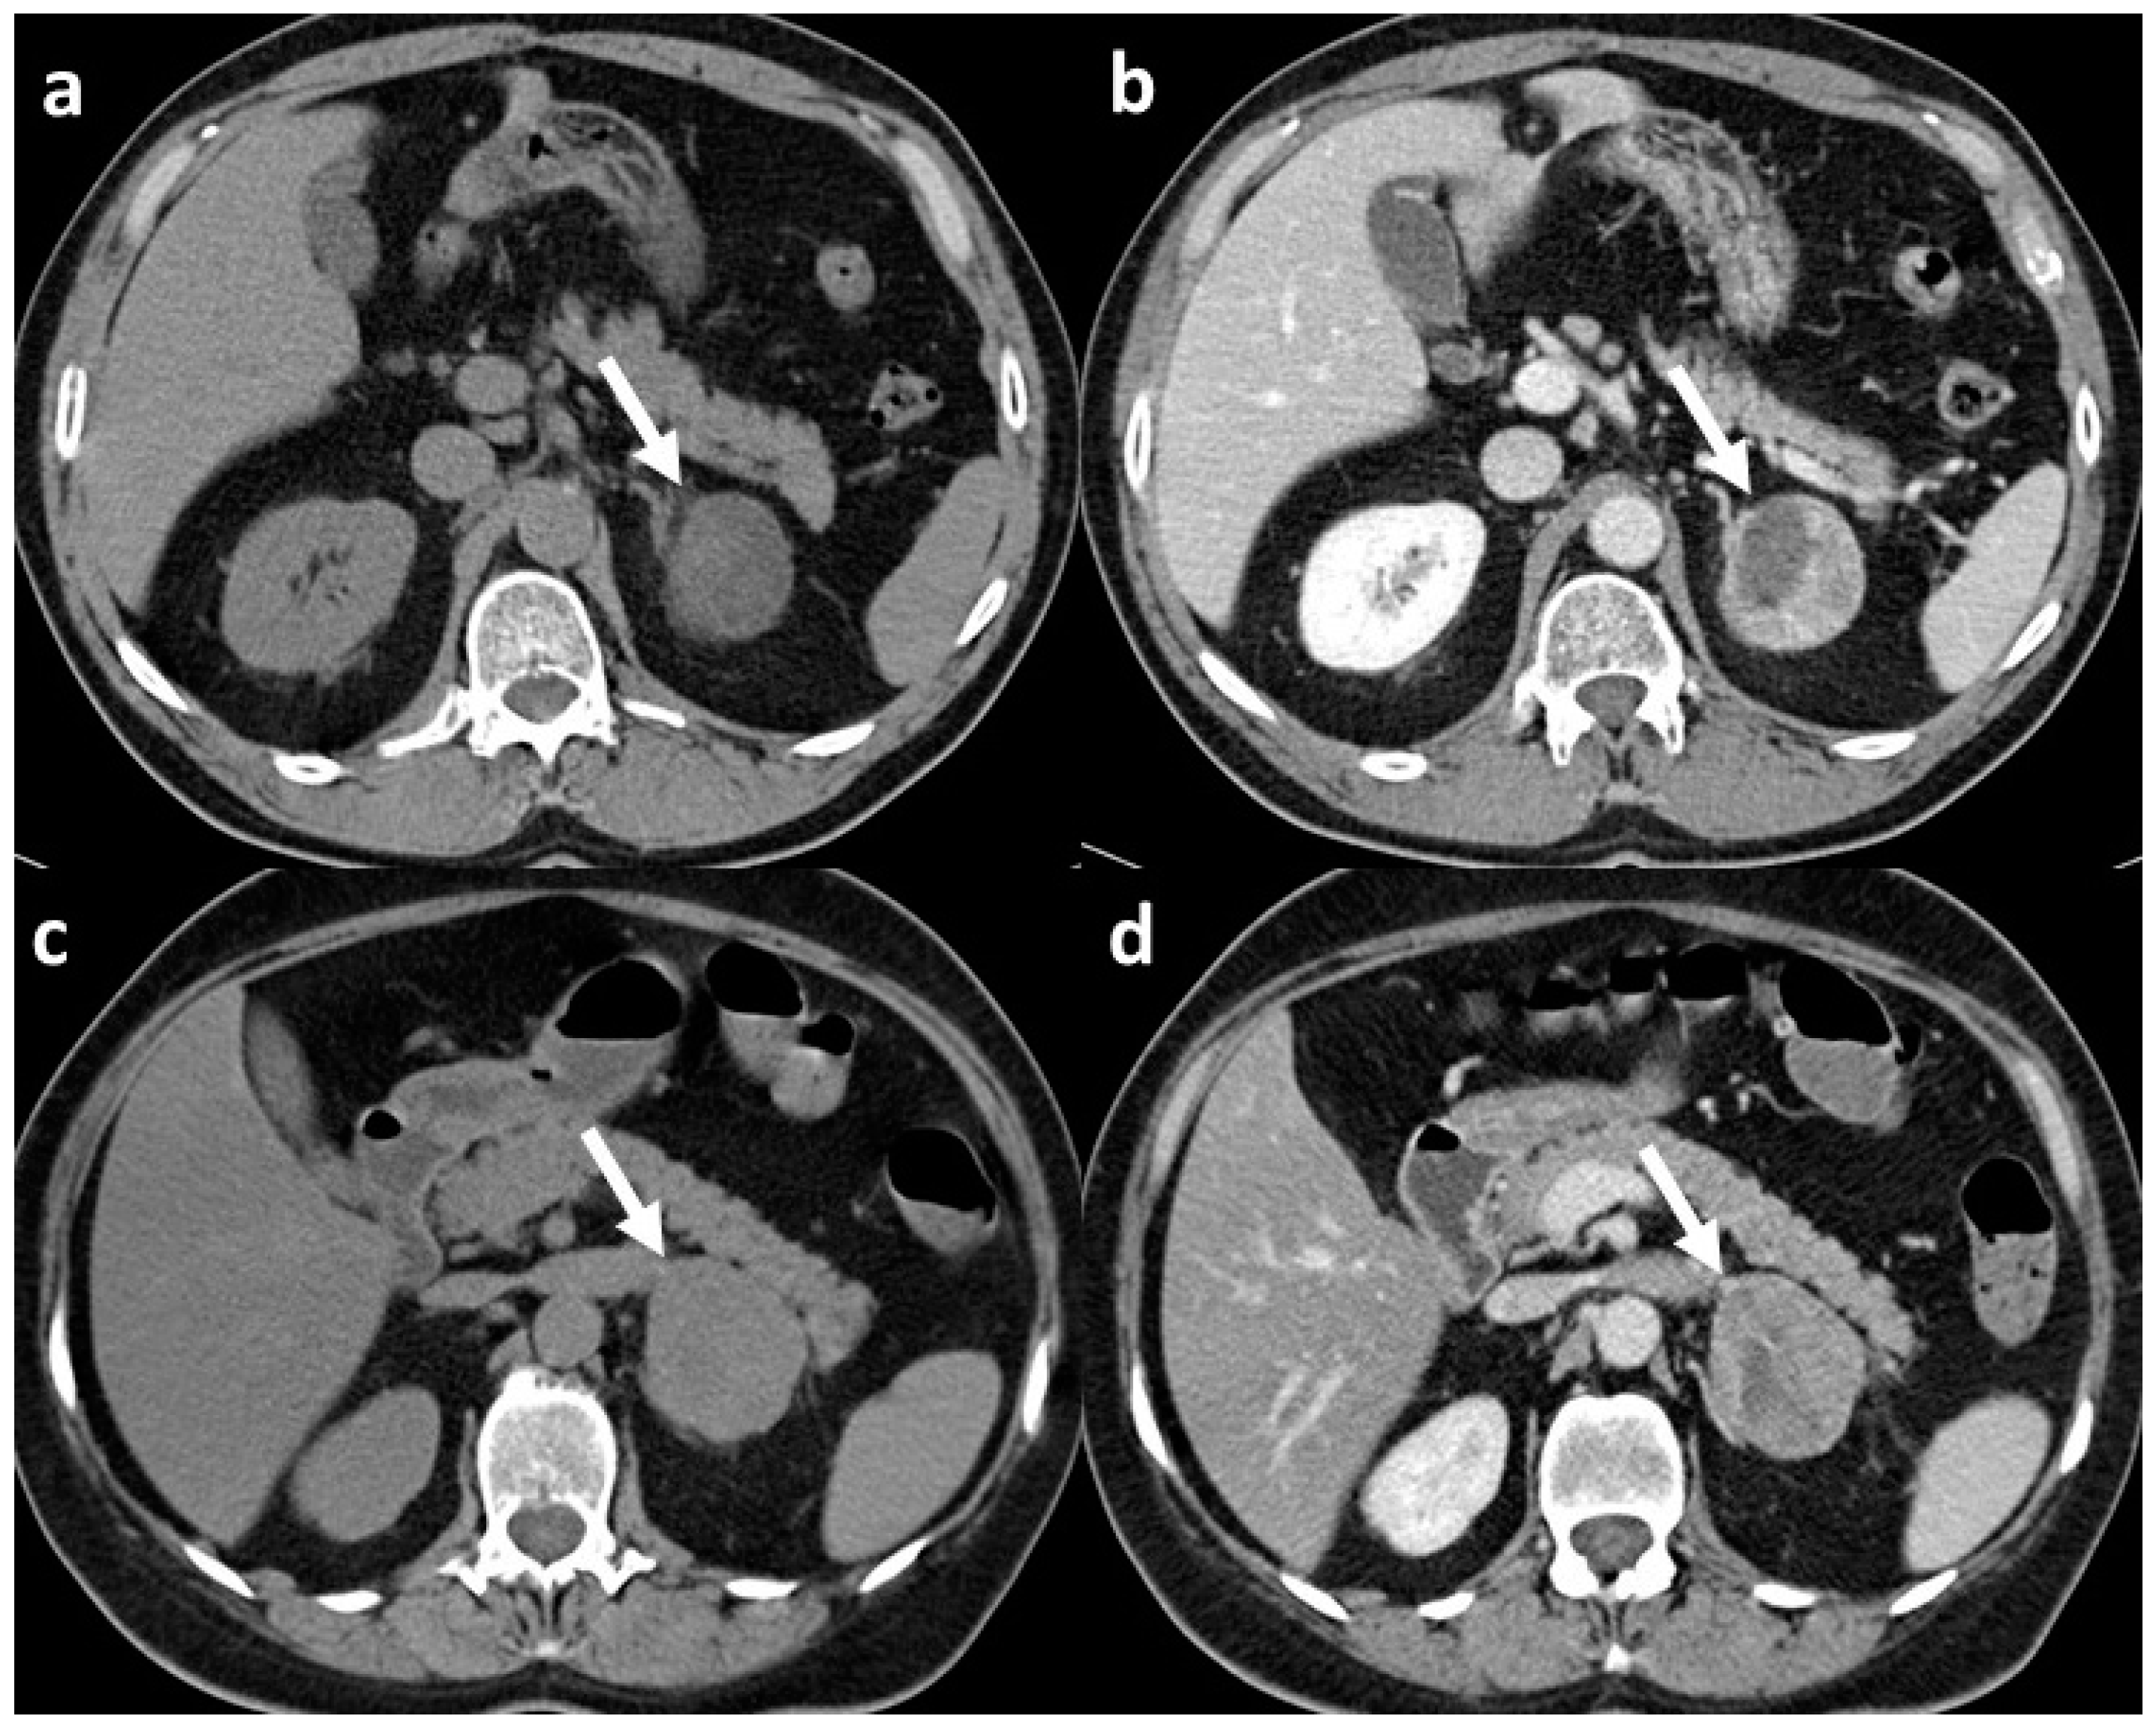

- Shi, B.; Zhang, G.M.Y.; Xu, M.; Jin, Z.Y.; Sun, H. Distinguishing Metastases from Benign Adrenal Masses: What Can CT Texture Analysis Do? Acta Radiol. 2019, 60, 1553–1561. [Google Scholar] [CrossRef]

| Shi B | 2018 | Observational retrospective | 225 | Lipid poor adenomas, metastases, pheochromocytoma | +/+ | 2 | Yes | Histology | TexRAD | 0, 2, 3, 4, 5, 6 | 5/4 | 0.81 |